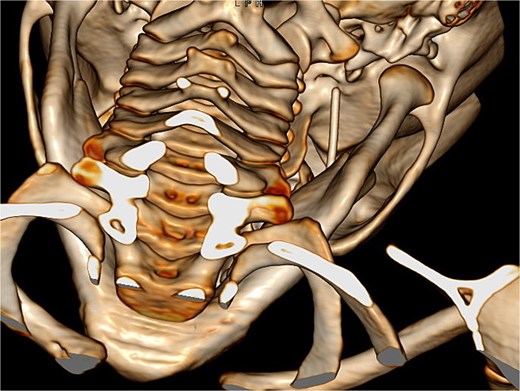

Once in the operating theatre, a CBCT was performed before starting the procedure to assess the precise position of the needle. Surprisingly, the needle had migrated, likely due to masticatory function, and had traversed the foramen ovale into the middle cranial fossa, below the right temporal lobe (Fig. 2). A neurological re-evaluation reported no neurological deficits. Given the new location of the needle, the surgical plan was revised in consultation with neurosurgeons, and the parents provided consent for a neurosurgical approach. It was agreed to perform intraoperative angiography and angio-CT to assess the integrity of the Circle of Willis.

Intracranial CT scan showing the intracranial migration of the needle through the foramen ovale.